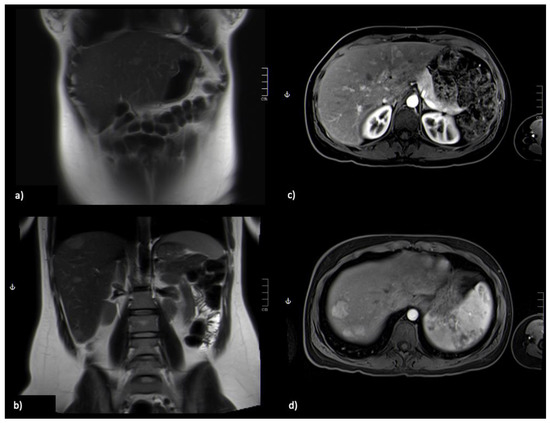

The MRI 6 months later showed a global decrease of the largest nodules, ranging from a 3 to 9 mm reduction (Figure 3). She has been followed for two years now and the lesions are stable, with roughly the same dimensions.

Figure 3.

Re-evaluation, comparative with Figure 1, dimensional improvement of nodular lesions; (a,b) Coronal section, lesion is hyperintense on T2-weighted image; (c,d) Axial GRE 3D FS T1-weighted sequence post-Gadoxetic acid intravenous administration at arterial phase, with hyperintense lesions.